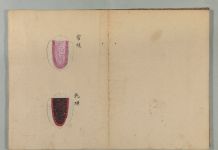

胸脇苦満ノ毒、浅薄ナル者ノ圖也。

按之而知ノ傳、圖ノ如ク、

脇下肋骨ノ端ヲ指ニテカヽゲミルニ、コタユルモノアリ。

是薄キ苦満ノ毒ナリ。

又、心下ヲ按テ少シクコタユルモノナリ。

是即痞鞕ナリ。世二積聚ト号スルモノ、此ノ證多シ。

又圖ノ如ク、苦満アリテ、心下痞硬甚シキモノアリ。

此時ハマヅ苦満ヲサシ置テ、痞鞕ヨリ攻ベシ。